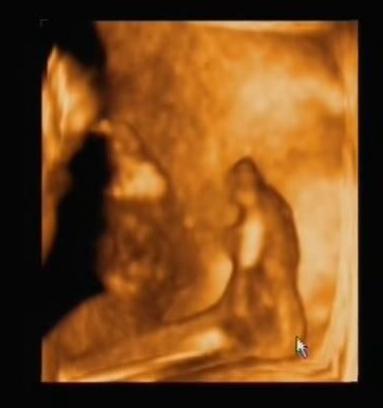

És képzeljétek, amig néztük őt uh-on, iszogatott a magzatvízből.

Nyitogatta a kicsi száját, és a doki még a nyelőcsövét is megmutatta, hogy látszódik a folyadék ahogy nyel...

A magzatvizet iszogatom...